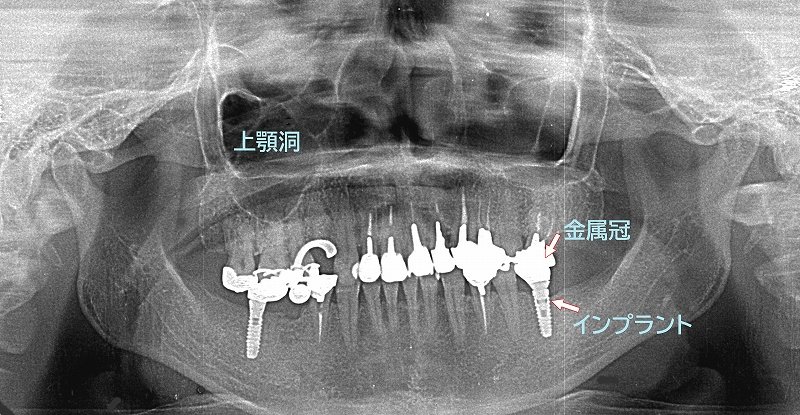

当院は、日本口腔インプラント学会の専門医・指導医が在籍する信頼の歯科医院です。難症例や多数歯のインプラント治療において豊富な実績があり、他院で断られたケースにも対応しています。

特に、サイナスリフトや骨造成といった高度な治療技術を駆使し、患者様一人ひとりの状況に最適な治療法をご提供します。専門的な知識と技術で、複雑な症例にも安心してお任せいただけます。